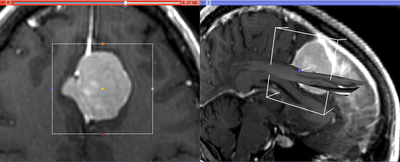

This module allows to extract rectangular subvolume from a scalar image, with the subvolume defined by Slicer ROI widget.

- Input ROI is a Region of Interest (see the ROI module documentation), which can be defined outside CropVolume, or by creating new ROI by using the Mouse Interaction toolbar (selection ROI mode and clicking on two points in a slice or 3D view). The ROI can be adjusted using the widget handles in slice and 3D views. ROI can be rotated/translated using a transform.

Cropping of oblique sub-volumes can be done by placing either or both of input volume and ROI under transform(s). These transforms will be taken into account while preparing the output.